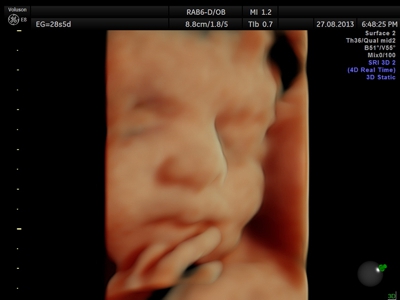

Fotografías de ecografías 4D HD/5D

Haga click sobre las imágenes para ampliar